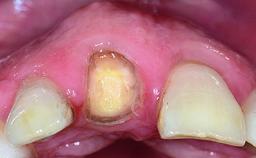

Replacement of a Failing Upper Right Central Incisor, Ridge Preservation and Late Placement of a NC Bone Level Implant

A 30-year-old patient presented at our clinic with a chief complaint of pain in her endodontically treated right maxillary central incisor (tooth 11) with a post-and-core and a fixed single crown. She had a very high lip line, a medium to thin soft-tissue phenotype, and a medium scalloped gingival contour. She also had high esthetic expectations because of her young age and beautiful smile. However, her expectations were realistic and she understood the risks of the treatment. At the initial clinical examination there was a slight mobility of tooth 11; no fistula was observed. The patient also had a single crown on the adjacent tooth 21. Both restorations were old and esthetically deficient. A digital periapical radiograph showed a very small periapical radiolucency, a thick intraradicular post, and no separation between root fragments.